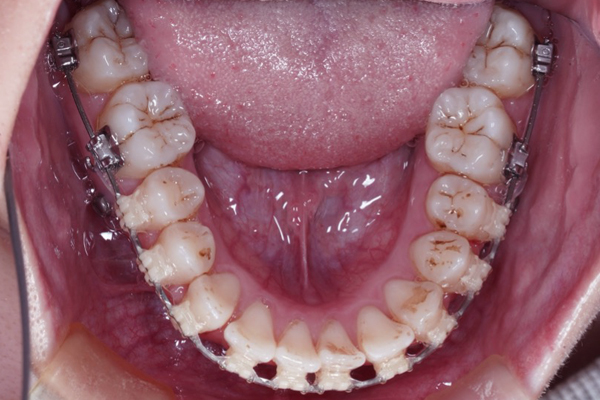

AFTER

【3ヶ月経過の変化】

• 前歯の重なりが減り、アーチが広がってきました。

• 下の歯はほとんど並びました。

• 見た目も変化してきて患者様も喜んでいます。

現在3ヶ月の段階でも、ガタガタがしっかり改善してきています。